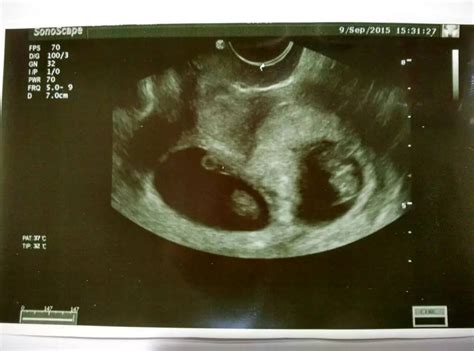

对于胎停育的诊断标准是,胚胎发育≥6周无妊娠囊,或虽有妊娠囊但变形皱缩;当妊娠囊≥4cm却看不到胎芽,胎芽的头臂长度≥1.5cm却无胎心搏动,即可判定胚胎发育异常。

你好: 发生胚胎停育大多数孕妇胎儿停止发育后无明显症状,部分孕妇可能见红,一般无腹痛,这与先兆流产不同。 病人有停经史,无论有无见红,在孕早期均应行B超检查,以免漏诊胎停育。B超监测胚胎,胎儿发育,如≥6周无妊娠囊,或虽有妊娠囊但变形皱缩,当妊娠囊已≥4cm却看不到胎芽,胎芽的头臂长度≥1.5cm却无胎心博动,即可判定胚胎或胎儿发育异常。后三种情况可以诊断为胎停育。另外血β-hcG测定也有助于胎停育的诊断。如≥5周,血β-hcG<100IU/L;≥6周,血β-hcG<2000IU/L,m提示绒毛膜促性腺激素分泌不足,动态观察其值不再上升者,则可判定绒毛上皮衰退,胚胎异常。 你的情况,孕68周,孕囊约1.9*1.0cm这么小,囊内有回声,但看不到胚芽组织及原始心管搏动,左侧卵巢大小4.4*3.9cm其内可见4.0*2.8cm的无回声区,考虑胚胎停育或胚胎发育异常,建议严密观察,到正规医院检查,明确诊断,及时处理。f